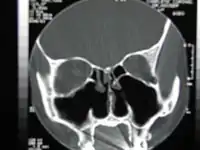

Tomografía computarizada de la nariz después de una turbinectomía bilateral total.